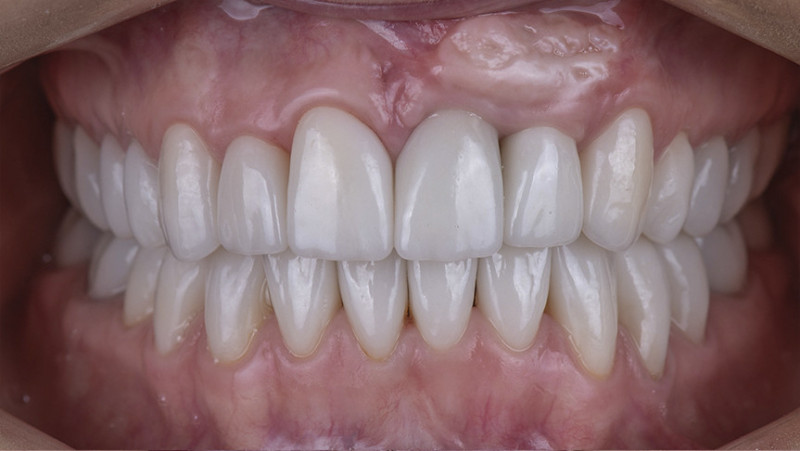

Установка керамической коронки

Изготовили и установили 22 керамические коронки EMAX и 6 виниров на нижнюю челюсть. Провели пластику десны в области 22 зуба. Устранили сильную рецессию десны в области имплантата, установленного в другой клинике.